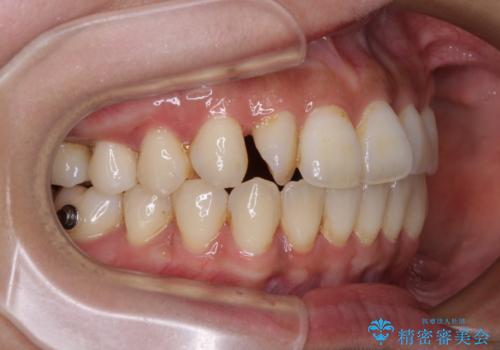

【モニター】上顎前突と奥歯の鋏状咬合 補助装置を用いたインビザライン矯正治療

- 前歯の歯列不正と奥歯の咬みにくさを気にして来院された患者様です。

インビザラインでの矯正治療を希望されていましたが、奥歯の咬み合わせがインビザライン単独では改善困難と判断されたので、補助装置を併用することとしました。

上顎最後臼歯は極端に外側を向いており、下顎骨に対して上顎骨が前方に位置していたため、補助装置により最後臼歯を一気に内側に引き込むとともに、上顎臼歯を後方移動させ、奥歯の咬み合わせが改善した後に、上下インビザラインにより歯列全体を整えていくこととしました。

奥歯の咬み合わせを事前に望ましい位置に改善したことで、インビザライン単独では改善が最も困難な状況を排除することができ、非常に理想的な仕上がりとなりました。